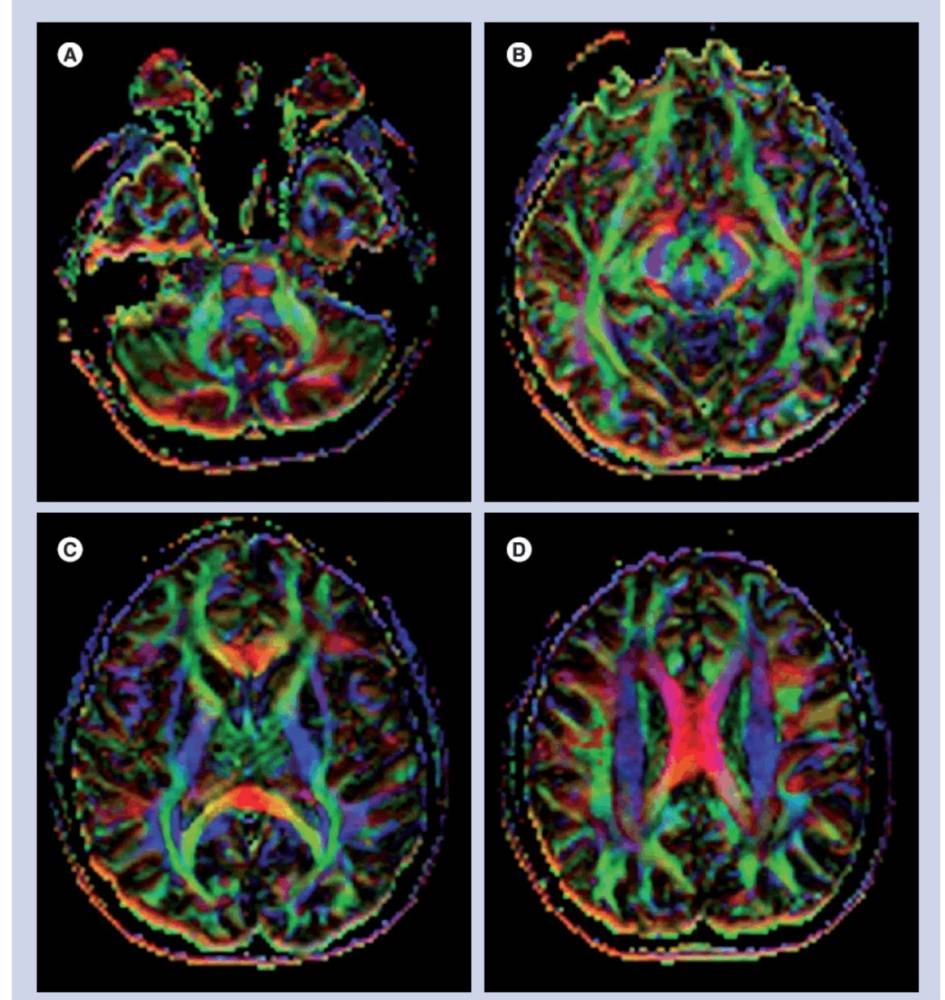

دراسة أسترالية تكشف: دماغ اللاعب يتغيّر بعد دقائق من ضرب الكرة بالرأس